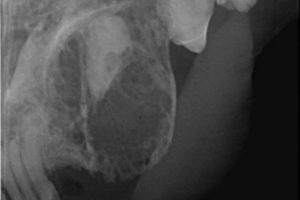

Hier waren die Zahnkronen bereits vor längerer Zeit verloren gegangen. Der Kater hatte jedoch Schmerzen: er hat sich immer wieder die Wange aufgekratzt. Erst als die Wurzeln entfernt waren, hörte er damit auf.